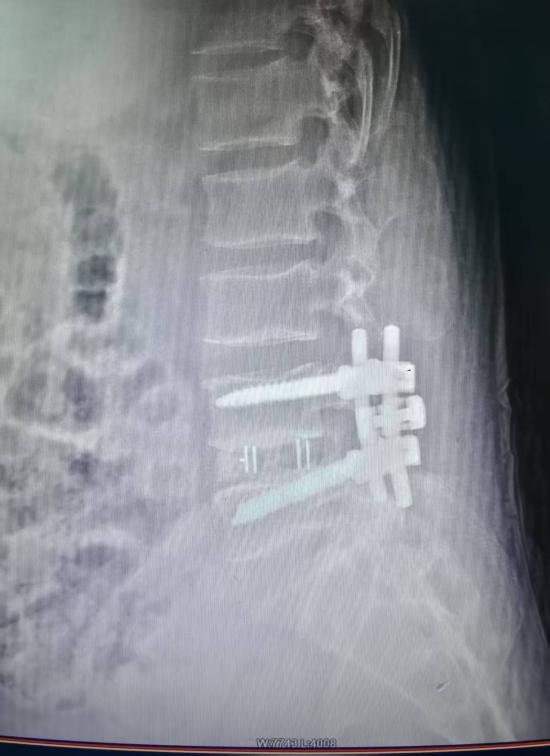

脊柱病区以脊柱疾病的微创化、精准化治疗为核心发展方向。开展颈肩腰腿痛等疾病的阶梯化治疗。常规开展椎间孔镜下腰椎间盘突出髓核摘除术、单侧双通道脊柱内镜(UBE)下融合术、经皮椎体成形(PVP/PKP) 、颈椎前路减压融合术、后路椎管成形术等,开展经皮与开放椎弓根螺钉内固定术,高效地救治各类复杂脊柱骨折与脊髓神经损伤。